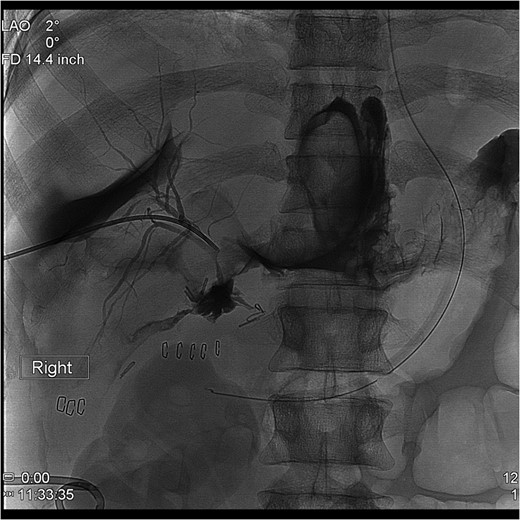

The PTC study confirmed the presence of a completely transected duct, and, fortunately, the ductal injury was traversed with a wire with entry into the distal ductal orifice and into the duodenum (Figs 4–6). Following the procedure, the patient was taken directly to the operating room for open surgical repair.

Percutaneous Transhepatic Cholangiogram with wire traversing into the distal common bile duct orifice. Note duodenum filling with contrast.